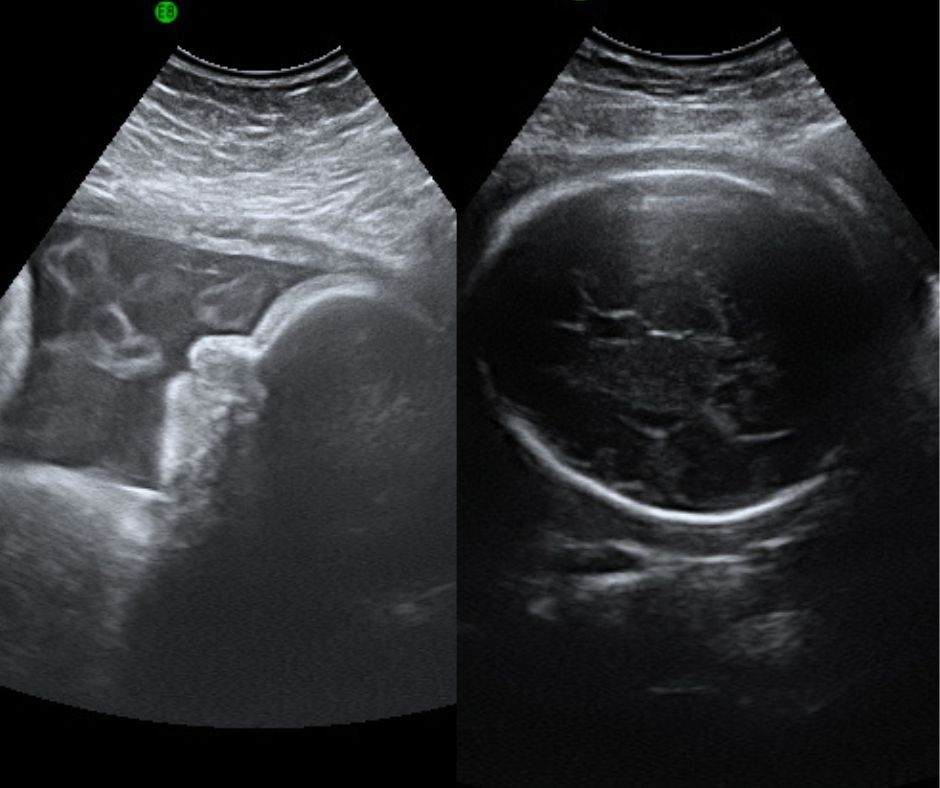

Presentation Scans

One of the great benefits of ultrasound is the possibility to follow the progress of your baby through gestation up to shortly before birth.

Presentation scans are generally carried out at 32-38 weeks of gestation, as your baby approaches birth date.

At this advanced stage it is usually possible via the ultrasound to:

• see the position of the baby

• see the size of the baby

• closely estimate the weight

• see the volume of amniotic fluid